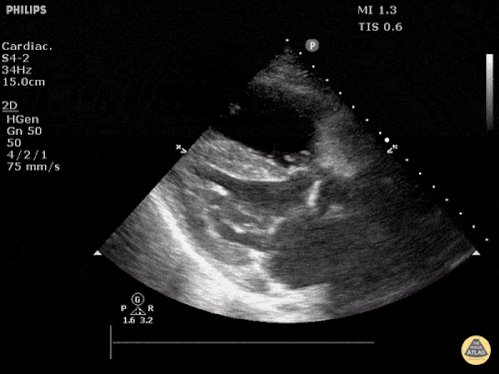

Making a thread of some POCUS gifs from @thepocusatlas

Will be referring to these during a basic POCUS workshop where learners practice scans on normal volunteers.

Non-scanning learners can pull up and show some abnormal examples in parallel with live demo of normal findings

00 - Normal parasternal long-axis (PLAX) view

01 - LV dysfunction in PLAX

02 - RV dysfunction in PLAX

03 - Tamponade in PLAX

04 - Mitral valve vegetation seen in PLAX

05 - Descending aortic dissection seen in PLAX

All images above from thepocusatlas.com , an amazing resource.